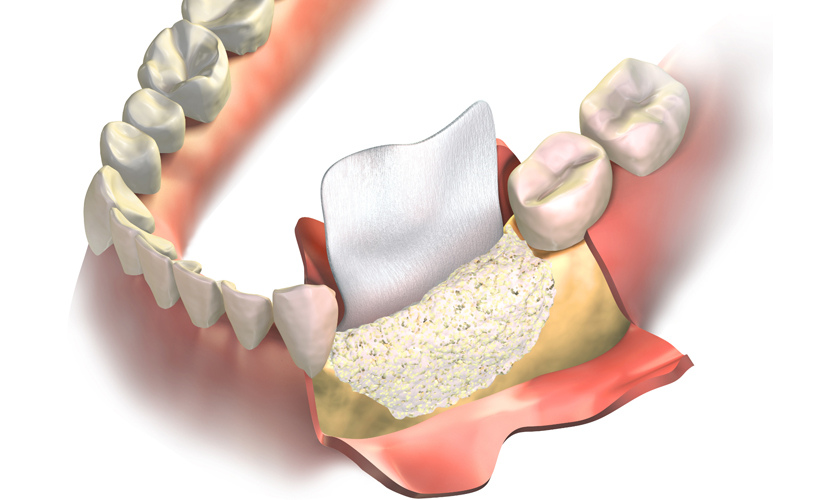

3. 牙周再生術:當齒槽骨破壞程度較深,在條件允許的前提下,醫師會建議進行齒槽骨重建。牙周醫師在清創後,會在齒槽骨缺損處填補骨粉,必要時在牙齦與齒槽骨之間置入再生膜,引導牙周組織再生,修復受損的齒槽骨,使牙齒恢復穩定性及支撐力。